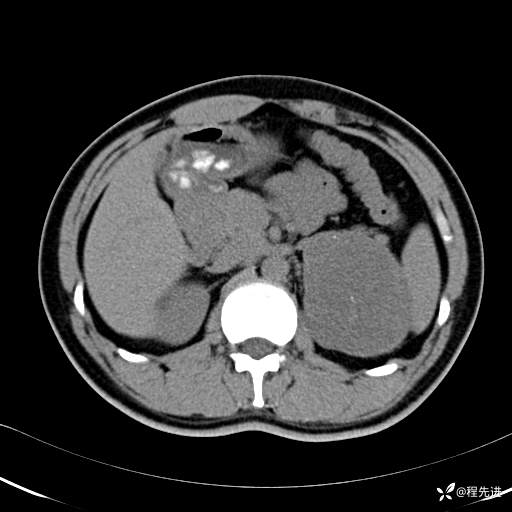

CT平扫:(CT值:平扫,27HU,动脉期,27HU,门静脉期,31HU,平衡期,32HU)

CT增强:

平衡期:

冠状位重建: